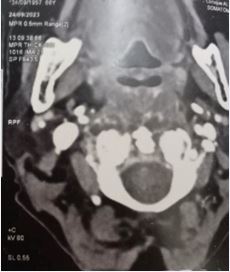

71-year-old women consulted with medial dysphagia during 13 months. She reported a foreign body sensation and actually the perturbance was important and imposed a modification of food ingrain (liquid foods). The global status of this patient is good (memory, hemodynamic constants, cardiac and renal functions). She reports an amigrissement of 8 kg without perturbance (asthenia). Clinical exam revealed a 5 X 4 cm mass in the posterior part of oropharyngeal way. Mucous was well without ulceration. Palpation was not pulsate and not painful. Fibroscopy not shows a nasopharyngeal or hypo pharyngeal extension. The lesion was strictly medial without lateral (para pharyngeal extension). Cervical and cranial nerve evaluation was normally. Enhanced computed tomography showed limited tumor of oropharyngeal space (Figure 1,2).

Figure 2 Coronal CT scan, retropharyngeal tumor with oropharyngeal expression.

MRI revealed a 5X4, 5 cm mass occupied retro oropharyngeal space without osteolysis (cervical spine) (Figure 3,4).

Clinical exam shows a mass (variable dimension) in oropharyngeal wall (retropharyngeal space) recovered by normal mucosa aspect (broken or bleeding mucosa is rare). CT scan is the first imaging exam. He shows the mass (location) and authorizes mensuration, extension, vascular characterization, and cervical spine reaction (lysis). In MRI, the chordoma signals are commonly iso intense or hypo intense on T1-weighted images and hyper intense on T2-weighted images.